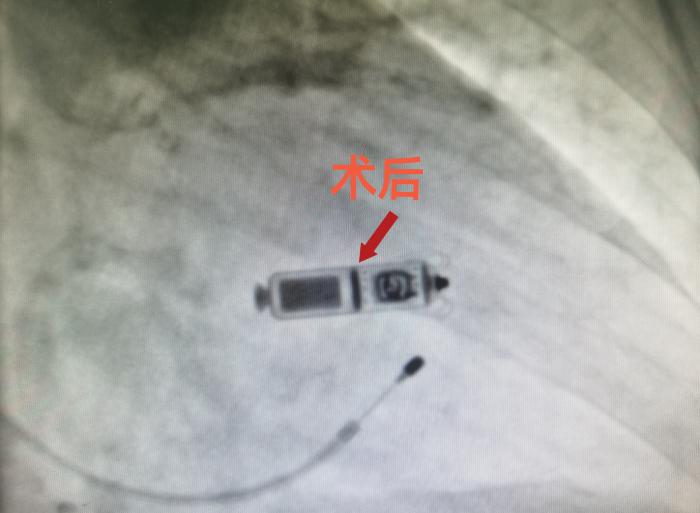

经老人及家属同意后,周玉庆副主任医师为陈奶奶实施了双腔无导线心脏起搏器(Micra AV)植入术,穿刺股静脉后,将无导线起搏器经导管顺利植入心脏,术中一次性释放,手术过程不到1小时。术后1天,老人家便可下床活动。陈奶奶全家都对治疗效果相当满意。